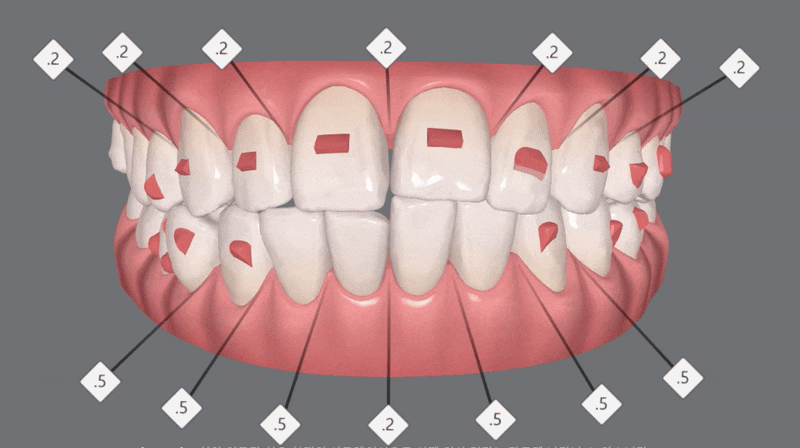

인비절라인라이트 (Invisalign Lite) 옵션은

인비절라인 컴프리헨시브 (Invisalign Comprehensive)옵션까지

할 필요는 없는 케이스에 쓸 수 있고,

앞니부분교정에 해당됩니다.

총 14개 (+추가 14개)

총 28개의 장치를 통해

교정을 마무리 할수 있는

기간도 비교적 짧으며

비용도 다소 저렴한 것이

장점인 인비절라인 옵션입니다.

클린체크의 예상대로

교정이 마무리된

사진을

확인해보실 수 있습니다.